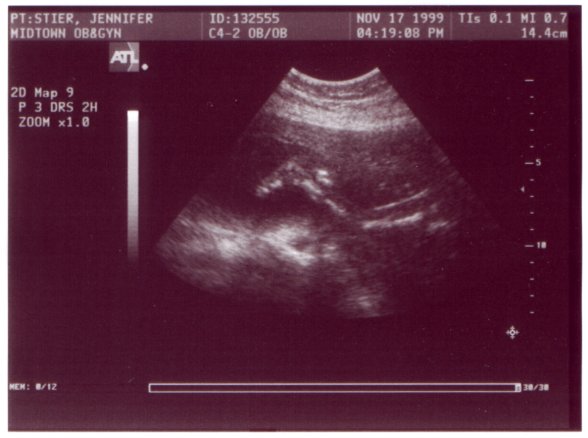

Ultrasound Picture No. 4